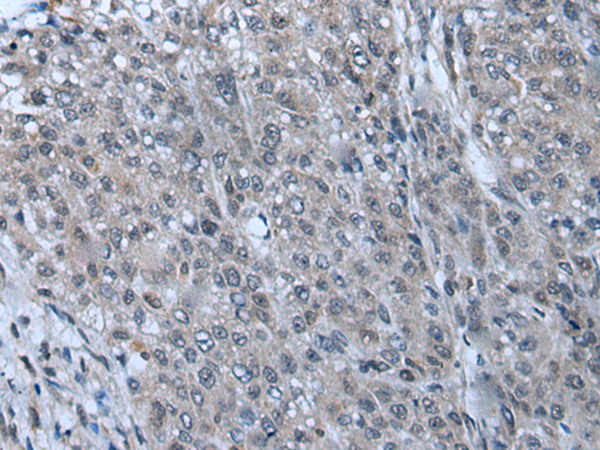

分类: 科研抗体货号: P12841别名: SBF; STAF; pHZ-1应用: IHC反应种属: Human, Mouse, Rat